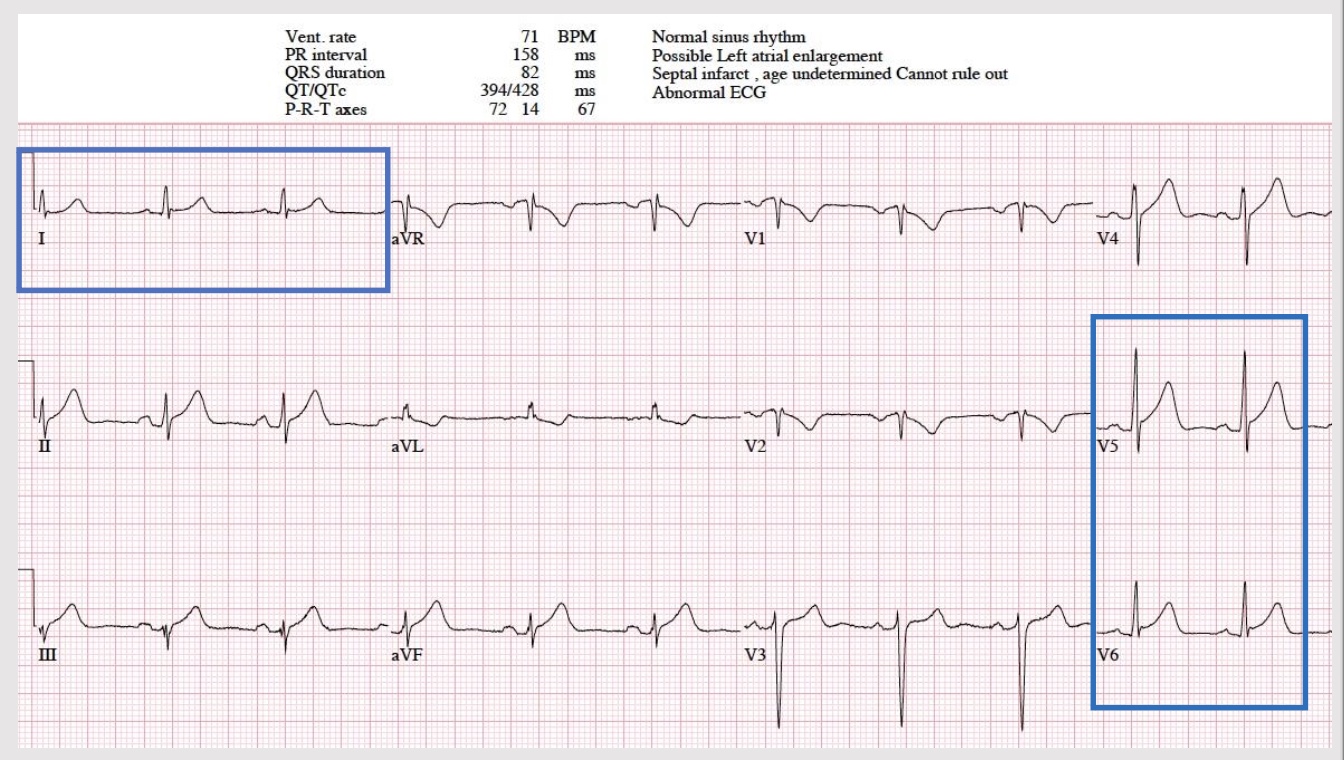

ECG findings

goal: complete within 10 min of presentation to ER

• primary diagnostic tool

• changes in QRS complex, ST segment, T wave → leave ECG leads on to continue to see changes and get worse/better

• dynamic process and evolves over time

• repeat ever 15-30 min to 2-4 hr

<p>ECG interpretation</p>

ECG interpretation

knowt flashcard image

anterior site of the heart

• indicitive: V1, V2, V3, V4

• affected coronary: L anterior descending

lateral site of heart

• indicative: 1, aVL, V5-6

• affected coronary: circumflex or LAD

inferior site of heart

• indicative: II, III, AVF

• affected coronary: R posterior descending

posterior site of heart

• indicative: reciprocal changes leads V1, V2, V3

• affected coronary: R posterior descending &/or circumflex